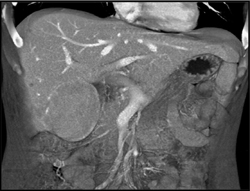

Hepatoma